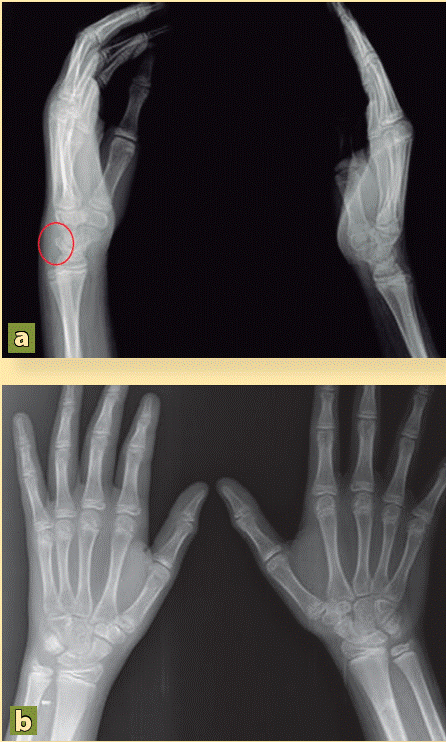

En las fracturas fisarias del cúbito existe una alta incidencia de cierre fisario prematuro 30-50 por lo que debemos controlarlo estrictamente. Fractura de Muñeca en Niños fractura Radiocubital distal es una de las fracturas mas comunes en niños ocupan el 45 y en el brazo ocupan el 62 66. En el caso de las fracturas de muñeca y de mano con un buen diagnóstico y un simple tratamiento incruento se soluciona el problema en la mayoría de los casos.

Considerada como una de las lesiones óseas más comunes entre niños y ancianos las fracturas de muñeca se asocian con las caídas ya sea durante la práctica de un deporte o por un resbalón debido a lo mojado o helado del piso. Las fracturas del carpo son infrecuentes en niños. Usted tiene preguntas o inquietudes sobre la condición o el cuidado de su hijo. About Press Copyright Contact us Creators Advertise Developers Terms Privacy Policy Safety How YouTube works Test new features Press Copyright Contact us Creators. La mayoría son fracturas en rodete o torus en las que sobresale la superficie ósea. Suelen ser tratadas con una tablilla de la muñeca o un yeso por debajo del codo. Reduccion de la fractura de muñeca en niños y adultos Actualizaciones ENYESADO ENTRE LOS 11 Y 12 AÑOS EN NIÑAS Y NIÑOS ENTRE LOS 12 Y 13 AÑOS GRACIAS.